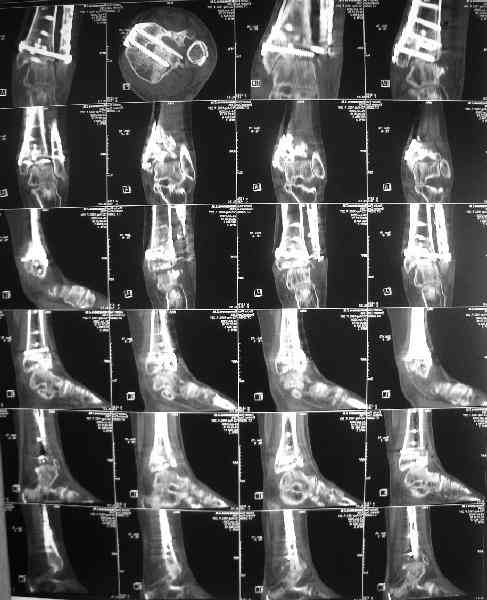

Dear коллеги, Обратилась женщина, 25 л. 8 мес. назад в одной из больниц сделан остеосинтез пилона. На сегодня ходит без дополнительной опоры, хромая на поврежденную ногу. Движения в голеностопном суставе еще есть. Снимки в приложении.

Вопрос - что делать? Замыкать сустав пациентка пока не настроена (наверно, получится настроить, если задаться такой целью). Нет ли смысла попытаться сделать какую-то восстановительную операцию? Допустим, получится устранить подвывих, восстановить межберцовые соотношения - это что-то хорошее надолго даст? Или упросто убрать "железо", и этим ограничиться, пока сама не придет за артродезом?

Есть ли здесь смысл пытаться организовать эндопротезирование? В смысле, доступные сейчас протезы применимы в этой ситуации?

A female, 25, 8 month ago operated elsewhere. To date walks without support with pain and limp. The ankle is mobile yet. Images attached. The question is what to do now? The patient is not very keen on ankle fusion (though likely could change her mind if necessary) Is it worth to try a reconstruction procedure and what kind? Maybe it allows to restore alignment and tibio-fibular relationship - will it provide painless limb for more or less significant time? Or just remove the hardware and leave her alone until she herself comes for fusion?

Are available total ankle implants suitable for the situation? If yes what one?